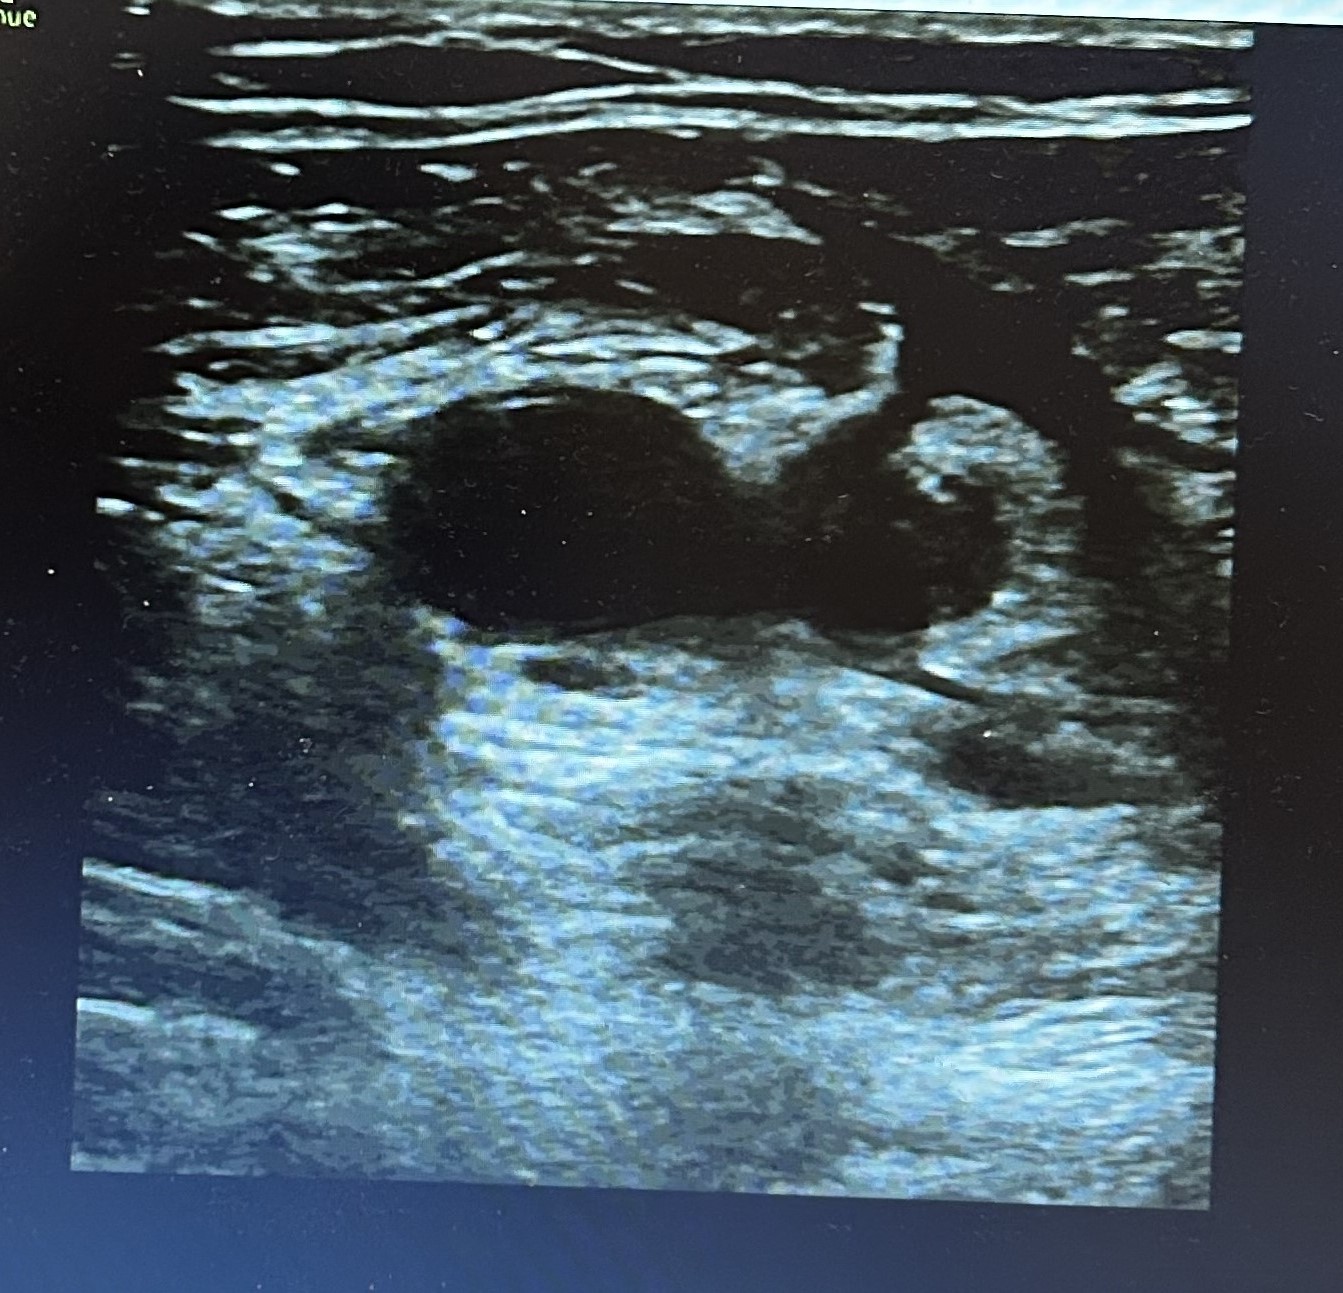

Hallazgos ecográficos

Ante cuadro sugerente de trombosis venosa se realiza ecografía-doppler venoso de la extremidad afectada objetivándose extensa Trombosis venosa profunda con afectación desde vena iliaca externa hasta territorio infrapoplíteo.